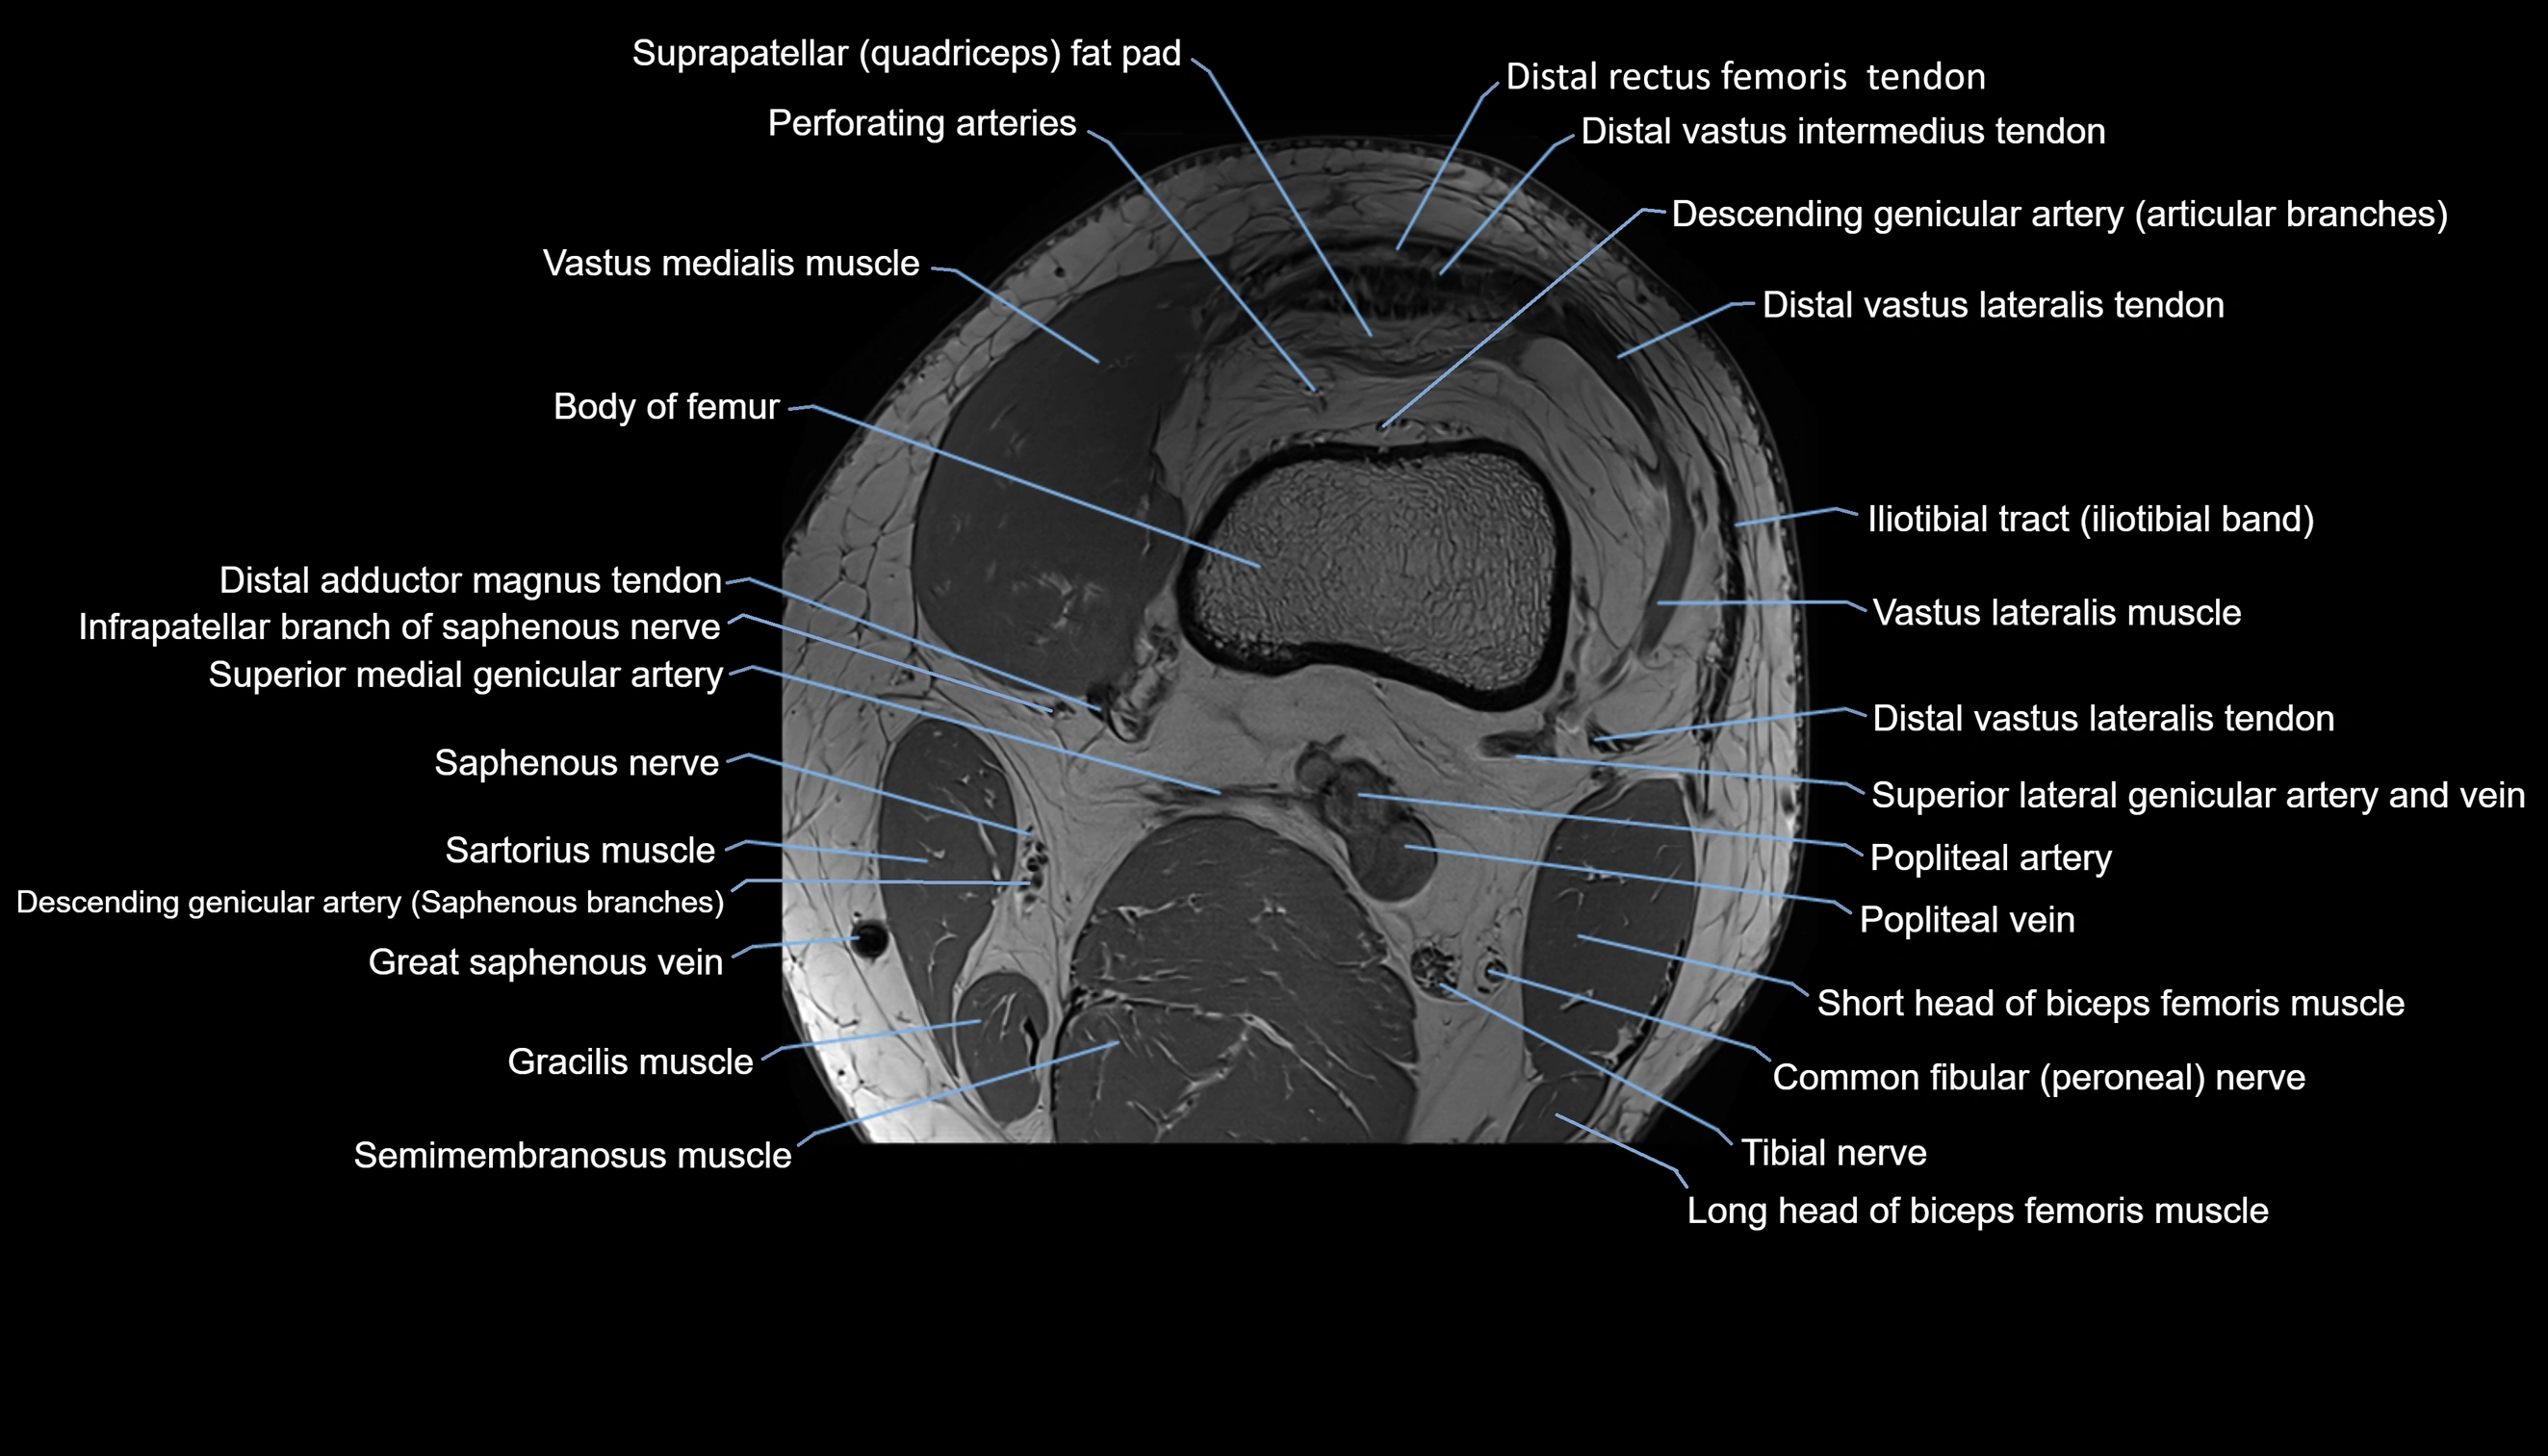

- Body of femur

- Descending genicular artery (Articular branches)

- Descending genicular artery (Saphenous branch)

- Distal adductor magnus tendon

- Distal rectus femoris tendon

- Distal vastus intermedius tendon

- Distal vastus lateralis tendon

- Infrapatellar branch of saphenous nerve

- Medial head of gastrocnemius muscle

- Perforating Arteries (Knee joint)

- Popliteal artery

- Popliteal vein

- Sartorius muscle

- Semimembranosus muscle

- Superior lateral genicular artery

- Superior lateral genicular vein

- Superior medial genicular artery

- Suprapatellar fat pad

- Vastus lateralis muscle

- Vastus medialis muscle